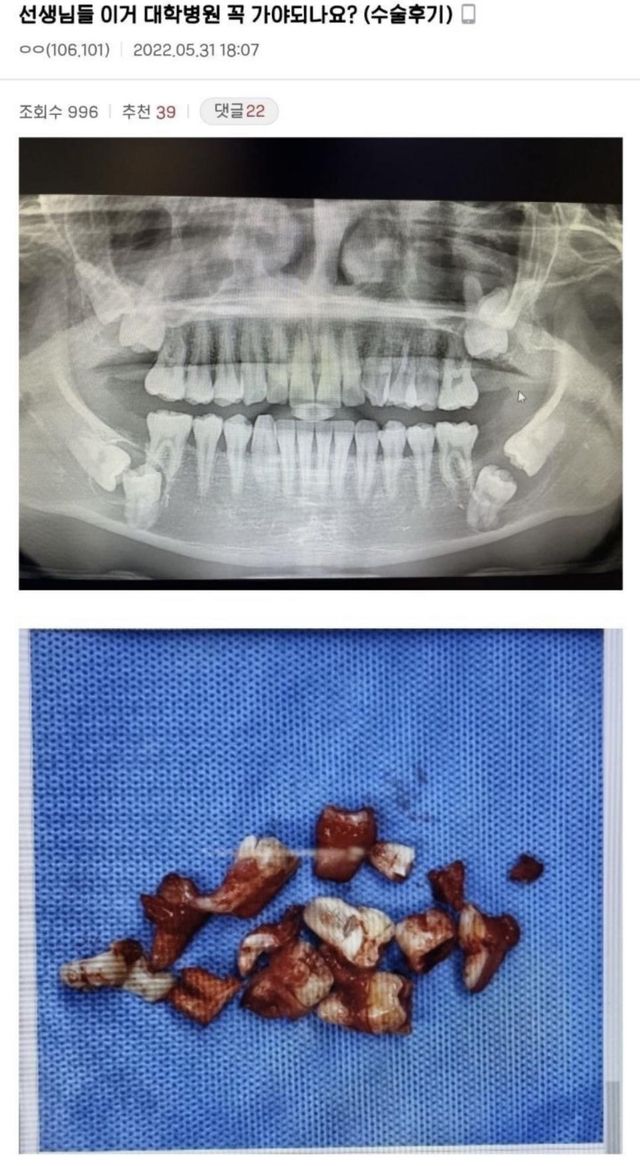

전생에 뭘 했길래사랑니가 저렇게 나?